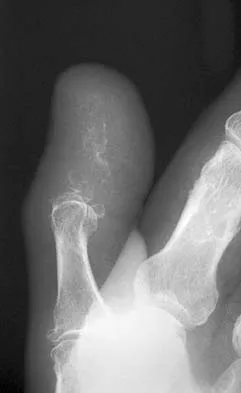

A 47-year-old woman falls and sustains a direct blow to her middle finger. She notes pain and swelling and is unable to move the proximal interphalangeal (PIP) or distal interphalangeal (DIP) joints. Radiographs are shown in Figures 8a through 8c. Proper management should consist of

The oblique nature of the fracture and extension of the fracture to the condyles implies an unstable fracture. Lag screw fixation provides an excellent chance of union, and the ability to start early range of motion. Stern PJ: Fractures of the metacarpals and phalanges, in Green DP, Hotchkiss RN, Pederson WC, et al (eds): Green's Operative Hand Surgery, ed 5. Philadelphia, PA, Elsevier, 2005, p 281.